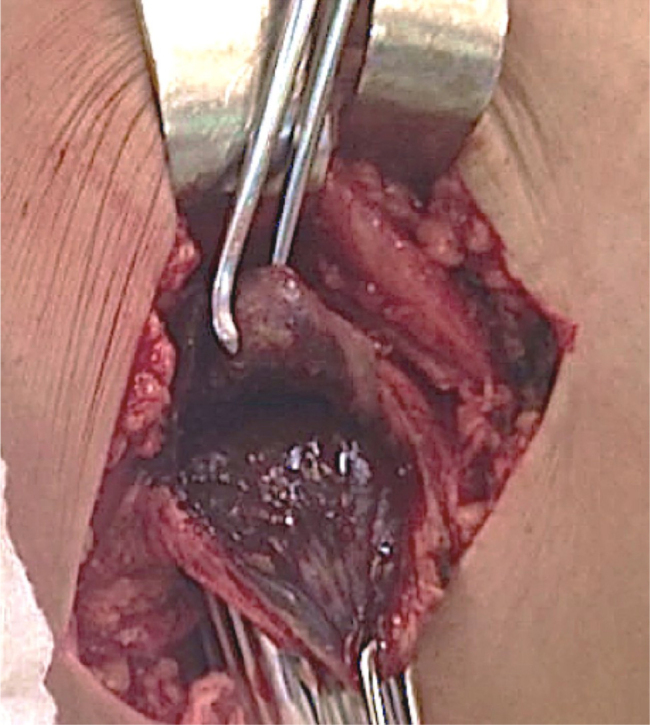

The patient was placed in the supine position with the aid of a cushion on the back of the left thigh. Through the two medial access routes, it was possible to achieve the emptying of a large amount of dark yellowish-green secretion, without distinctive odor or purulent aspect, with organized lumps (Fig. 4). After the emptying of the cystic contents, it was possible to identify the pseudotumor capsule with more precision (Fig. 5). This structure was preserved and its closure was carried out by approximation with spaced stitches and Mononylon 4.0™. Then, with the patient still in the supine position, the implant was removed using Hardinge's lateral approach. It was observed that the polyethylene insert was intact. Serum levels of chromium and cobalt were measured with the help of Instituto de Química da Universidade de São Paulo (Chemistry Institute of the University of São Paulo), using the graphite furnace atomic absorption spectrometry (GFAAS) technique. The cobalt level was not identified and the chrome level was 0.7 μg Cr/L (micrograms per liter), which is within the normal range. The measurement of chrome level in urine was performed at Instituto Adolfo Lutz. In the first sample, collected 1 week after implant removal, the absolute value found was 14.1 g/L. The second sample was collected 3 months after surgery, which also measured the metal ratio with urinary creatinine. The absolute value was 13.9 μg/L and the relative value of 6.7 μg Cr/g of creatinine, a slightly increased level. The patient was also submitted to the Harris Hip Score questionnaire before and after surgery, which showed an increase of nine points 2 weeks after surgery (54–63); the patient is currently asymptomatic and the surgical wound has a good aspect. The leukocyte count, ESR and CRP values are within the normal range (Fig. 4, Fig. 5).

Fig. 5.

Intraoperative image of pseudotumor capsule after emptying of the fluid contents. The dark aspect of its inner wall can be observed.